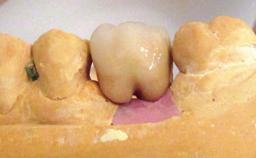

A 30-year-old female patient was referred to the Department of Periodontology of the University of Bern, Switzerland, by a dentist in private practice. Tooth 45 had been congenitally missing and had been replaced with a titanium implant three years prior to the first visit at the Department of Periodontology. The tissue level implant had a diameter of 4.1 mm, a length of 12 mm, and a sandblasted and acid-etched (SLA) surface (Straumann® Dental Implant System; Institut Straumann AG, Basel, Switzerland). The metal-ceramic crown on implant 45 had been cemented permanently. Implant 45 had been diagnosed with peri-implantitis by the referring dentist in the course of regular supportive care.